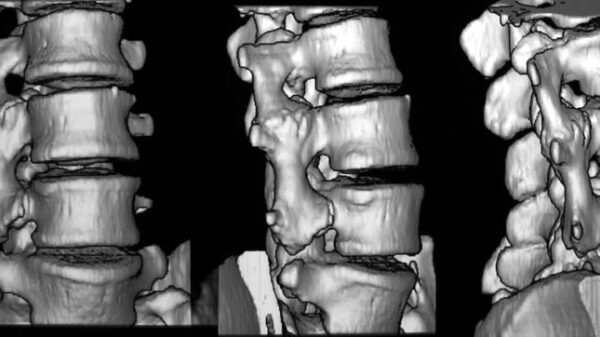

03 Frakturheilung. Knöcherne Brücken zwischen den lumbalen Querfortsätzen